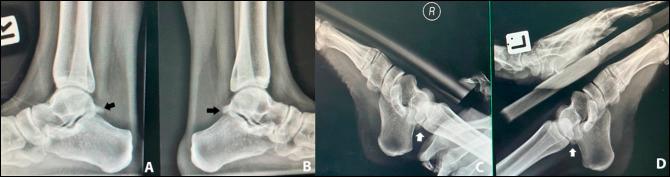

This is a case report of a 21-year-old female undergraduate student who sustained bilateral ankle injuries while jumping from a moving van wearing 3-inch high heel shoes. Upon initial presentation, her injury was treated conservatively as an acute bilateral ankle sprain for 6 weeks. However, the patient reported no improvement of pain and remained unable to self-ambulate. Bilateral MRI and CT scans of both ankles demonstrated bilateral os trigonum fractures. She underwent bilateral posterior ankle arthroscopic débridement of both os trigonum. At the postoperative 36-month follow-up, the patient reported notable improvement of all functional outcomes (36-item Short Form survey and Foot and Ankle Ability Measure), reported return to the same level of sports activities, and experienced no pain (visual analog scale) on either ankle. This is the first report in the literature of bilateral os trigonum fracture treated with simultaneous posterior ankle arthroscopic débridement.

这是一份关于一名 21 岁女大学生的病例报告,她在穿着 3 英寸高跟鞋从一辆行驶中的货车上跳下时,双侧踝关节受伤。初次就诊时,她的损伤被保守治疗为双侧急性踝关节扭伤,持续了 6 周。然而,患者报告疼痛没有改善,仍然无法自行行走。双侧踝关节的 MRI 和 CT 扫描显示双侧距骨后三角骨骨折。她接受了双侧后踝关节镜下距骨后三角骨清理术。术后 36 个月随访时,患者报告所有功能结果(36 项简短表格调查和足踝能力测量)均有显著改善,报告回到相同水平的体育活动,且双侧踝关节均无疼痛(视觉模拟评分)。这是文献中首例双侧距骨后三角骨骨折采用同期后踝关节镜下清理术治疗的病例报告。